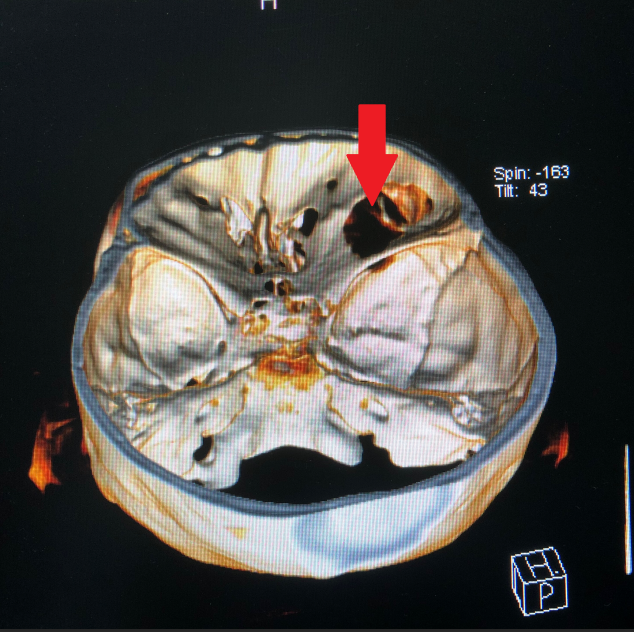

探花av 神经外科团队接诊后对患者进行了全面检查,诊断为右眼眶肿瘤。因患者肿瘤向颅内生长,颅底及眼眶骨质已完全破坏,传统的手术方式不仅创伤大,更可能因为颅底结构无法完全重建导致患者脑脊液漏,引起颅内感染。神经外科联合眼科进行了手术方式的讨论,根据术中可能出现的各种情况其制定了详细的治疗方案,认真完善术前准备后,于2018年12月24日成功为其开展“完整切除颅内外沟通瘤并颅底眼眶重建修复手术”,手术过程非常顺利,术后患者无视神经损伤,视力较术前明显改善。目前患者已康复出院。

颅底眼眶疾病是神经外科与眼科的交叉区域,我科该手术的成功开展,不仅标志着我科对眼眶骨折修复及颅底眼眶肿瘤手术新领域的开拓,也将为眼眶疾病的患者带来福音。